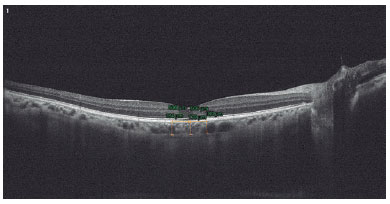

We assessed all participants using the RTVue RT-100 Spectral Domain OCT (Optovue, Foremont, CA, USA) device. We selected the line mode for choroidal imaging for choroidal assessment and took 12 mm cross-sectional images passing through the optic nerve and fovea center. We repeated choroid imaging twice for each eye. We measured systemic tension arterial pressures before each OCT exam. We took SFCT measurements on three sites: at the center of the fovea, on the 500-micron temporal portion of the center of the fovea, and on the 500-micron nasal portion. We performed SFCT measurements manually by measuring the distance between the outer edge of the hyper-reflective band of the retinal pigment epithelium and the inner boundary of the scleral hyper-reflectivity. All OCT scans were performed between 11.00 am and 13.00 pm to avoid choroidal thickness diurnal variations. In addition, for the analysis of SFCTs, we compared the average SFCT age distributions of the patients with those of 18 age- and gender-matched healthy controls. The same experienced physician performed all OCT scans and SFCT measurements and recorded the averages of the two measured SFCT values (Figure 2).

10-fig02.jpg)